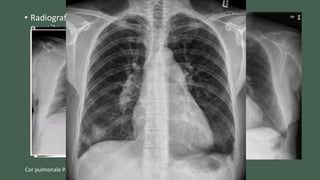

• Radiografía en proyección postero-anterior y lateral dado que

permite observar datos sugestivos de enfermedad pulmonar

como origen de la hipertensión pulmonar y evaluar

crecimiento ventricular derecho.